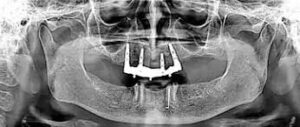

When a tooth is lost and plan to replace it with a dental implant, many times ‘bone grafting’ will be recommended for a stable foundation for that implant Called as preservation graft or socket graft.

Preservation of bone volume and architecture or shape is crucial for future dental implant stability and esthetics.

After an extraction there is a hole left in the jaw bone that is surrounded by tooth supporting bone. Body begins to absorb this bone if tooth is not replaced by an implant.

If the post extraction socket or whole is much larger than the implant or there is dental infection, a bone graft is needed to fill the space prior to placing the implant. The graft holds the volume of the space left by the tooth while the natural bone has a chance to fill the space with live bone.

Depending on the size of tooth, that was extracted, a bone graft may require between 3-6 months before an implant can be placed.

The material used most often for oral bone grafts is bovine bone (cow bone) that has been sterilized and is comprised only of the mineral content of the natural bone. This avoids the harvesting of the patient’s own bone as it was done in the past.